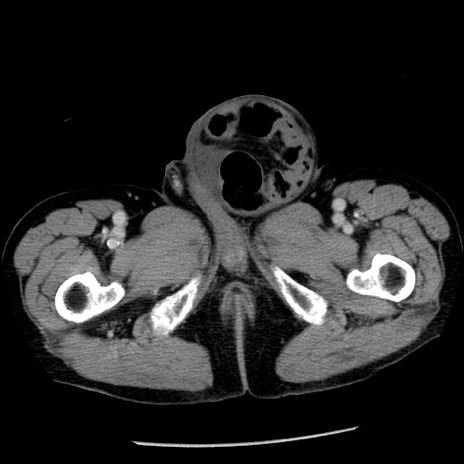

症例26(横断像)

【症例】80歳代男性

【主訴】嘔吐

【現病歴】昨晩2回嘔吐あり、今朝になっても嘔吐あり。来院。

【既往歴】胃潰瘍

【身体所見】意識清明、BT 37.6℃、BP 166/95mmHg、HR 100bpm、SpO2 97%、腹部:平坦・軟、腸蠕動音聴取良好、圧痛なし。

【データ】WBC 21900、CRP 1.46